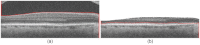

Segmentation of anatomical and pathological structures in ophthalmic images is crucial for the diagnosis and study of ocular diseases. However, manual segmentation is often a time-consuming and subjective process. This paper presents an automatic approach for segmenting retinal layers in Spectral Domain Optical Coherence Tomography images using graph theory and dynamic programming. Results show that this method accurately segments eight retinal layer boundaries in normal adult eyes more closely to an expert grader as compared to a second expert grader.